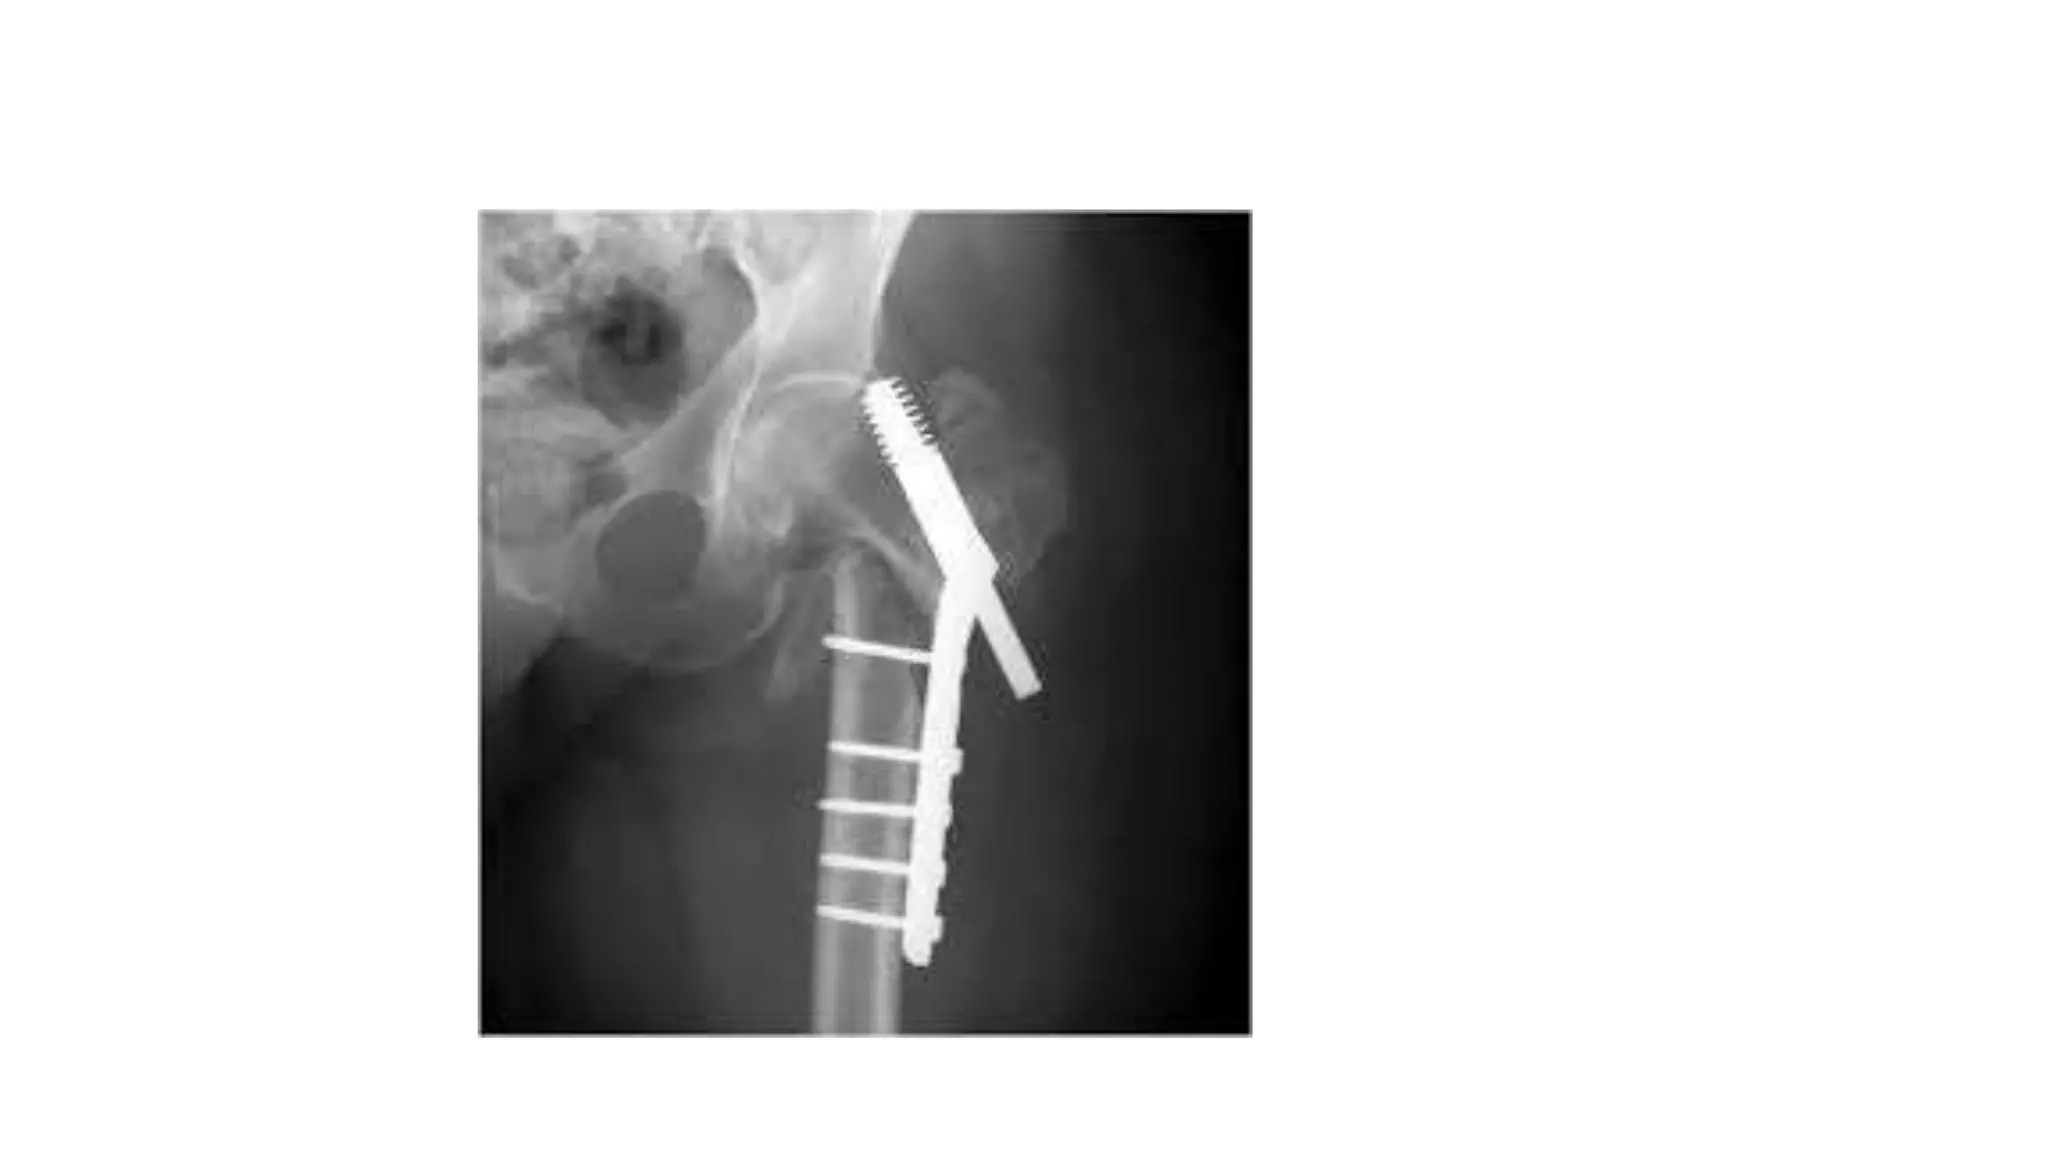

Complication

•

Dynamic hip screw